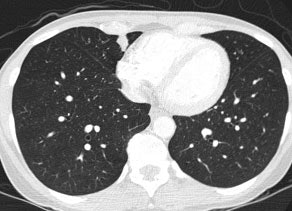

Bronchoalveolar cell carcinoma (BAC): The images below were from a patient with bronchoalveolar cell carcinoma that presented as a chronic right lung infiltrate. The FDG PET exam was positive in this case despite a higher likelihood of a false negative exams in patients with BAC. Note the most intense area of FDG accumulation corresponds to the area of greatest consolidation on CT imaging. |